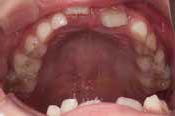

指しゃぶりのクセがあり、お口を閉じることができません

Aさん (矯正開始時:7歳)

Before

After

舌の位置が低く、上あごの天井が高くて狭い状態でした。鼻がつまりやすく、口をポカンと開けながら呼吸をしていることが確認されました。

治療を終えて

現在まだ治療継続中ですが、装置によって上あごを広げ、下の歯の位置を整える治療中です。お口のトレーニングにより鼻通りがよくなり、鼻呼吸が改善され舌の位置も正しくなりました。指しゃぶりのクセもなくなりました。

主訴・治療内容 指しゃぶりのクセがあり前歯が傾いていることから、お口を閉じることができないというお悩みで来院されました。

治療期間 1年

費用 495,000円(税込)